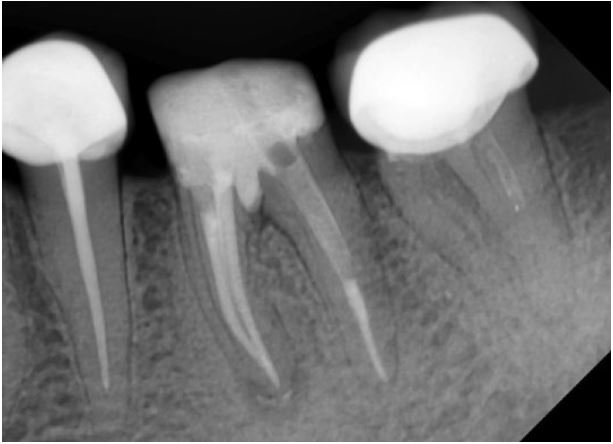

X quang R36 nghi ngờ thủng sàn tủy, vùng thấu quang quanh chóp chân gần và thấu quang vùng chẽ. R35 đã được điều trị tủy và phục hình, R37 điều trị tủy chưa đạt (H13.1).

Hình 13.11. X quang ngay sau điều trị.